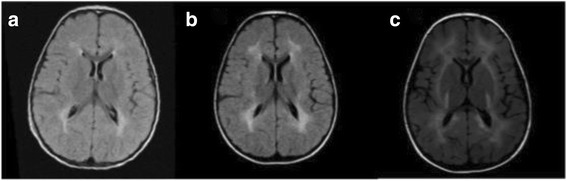

Brain MRI was performed in 6 CRIM-positive subjects (patients 11, 15, 19, 20, 23, 27). In one patient (patient 27) it was repeated at 2, 3 and 6 years of age, whereas in the other 5 the exam was performed only once at the age of 6 years. Imaging data showed the presence of moderate periventricular white matter abnormalities (hypomyelination) in all of them. Additionally, patient 27 showed a progressive deterioration of MRI parameters (Fig. 3), associated with the worsening of cognitive performances (Wechsler scales IQ: WPPSI 85 at 3 years; 75 at 5 years 10 months; WISC III 73 at 8 years, 64 at 9 years, 50 at 11 years).

Fig. 3.

Axial section T2 flair at the ages of 2 (a), 3 (b), 6 (c) years: white matter is progressively affected. In the last image the damage is extended to the posterior limb of the internal capsule and the subcortical white matter with U fibers. Basal ganglia are spared

Finally, an emerging finding in IOPD patients is the presence of periventricular white matter abnormalities [18–21]. We detected a pattern of hypomyelination in 6 children who underwent brain MRI. In one of them the exam was repeated 3 times during follow-up showing a progressive worsening of the lesions paralleling the development of a progressive cognitive impairment. A similar evolution has also been described by Ebbink et al. in other patients [19, 20]. These radiological abnormalities might be caused by neuronal glycogen storage [18] and the inability of the enzyme to cross the blood-brain barrier [28, 30] may justify the progressive cognitive and psychomotor worsening observed in these patients.